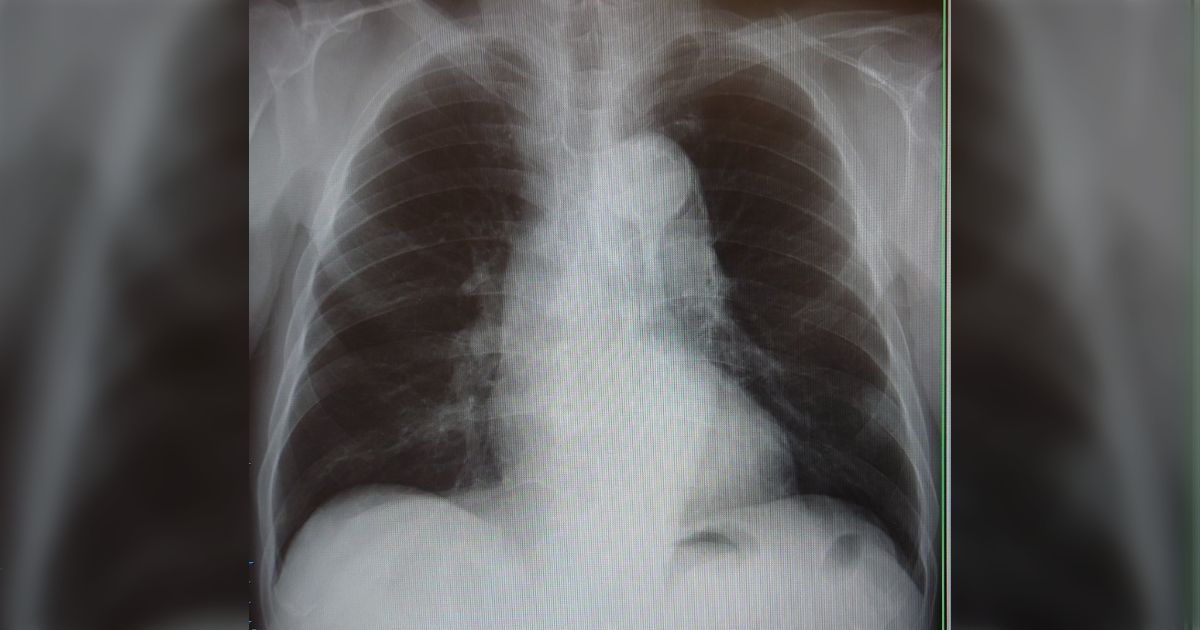

12. 肋骨の影と見分けがつかないような異変がAIによって見つけられた「これがなかったら診断遅れてた」

肋骨の影と見分けがつかないような異変がAIによって見つけられた「これがなかったら診断遅れてた」